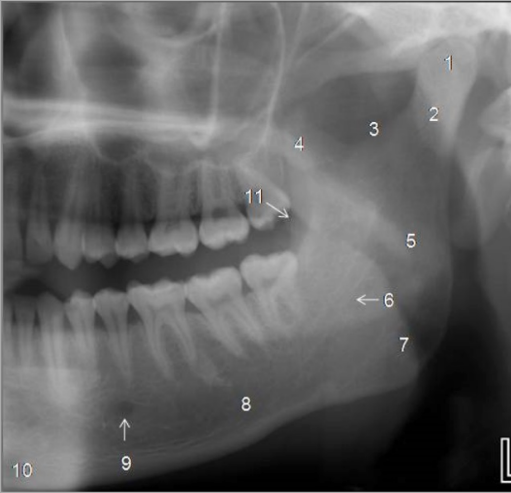

Identify The Structures On The Maxillary, Temporal & Zygomatic Structures.

Identify The Structures On The Mandible.